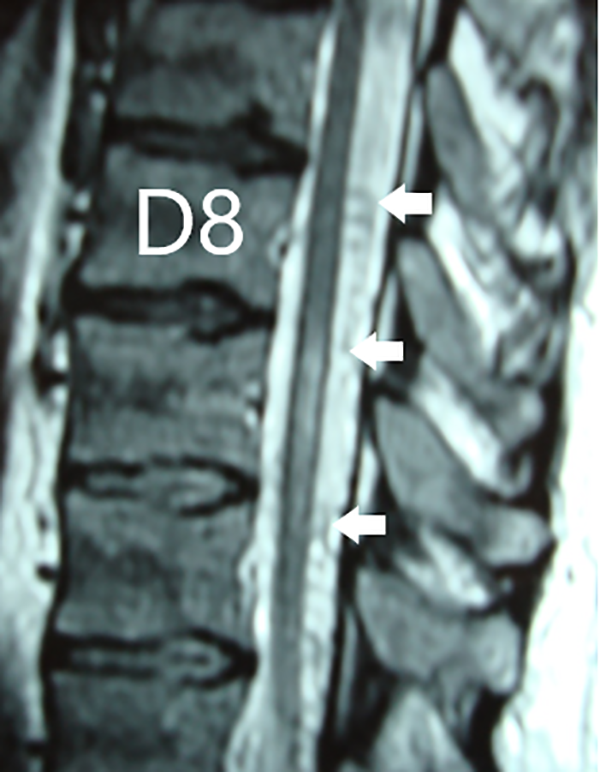

Figura 3: Caso #1. RMN sagital T2 que evidencia la hiperintensidad centromedular entre los segmentos D8-9-10 y la presencia de vasos dilatados perimedulares dorsales (flechas blancas).

Figura 4: Caso #1. ARM de alto campo en tiempo arterial que muestra a la arteria Aorta con sus vasos segmentarios y la presencia de una vena serpiginosa longitudinal (flechas blancas).